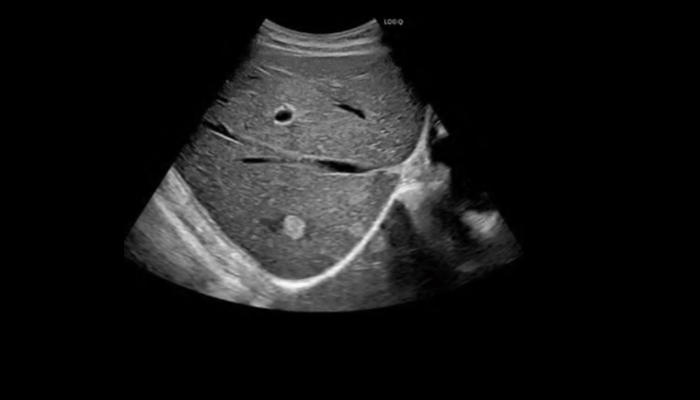

超音波により人体を可視化します。X線は使用せず、被ばくはありません。

乳房や甲状腺などの小さな病変や心臓、血管など動きのある臓器の診断に適しています。

エコー装置画像

エコー検査装置 エコー検査装置GE社製エコー検査装置 心臓エコー 心臓心臓の動きや心臓弁膜症を調べます。 乳腺エコー 乳腺高濃度乳房の方はマンモグラフィでは病気が見つけにくいことがあります。エコーと併せて評価をお勧めします。 腹部エコー 腹部肝臓、胆嚢、膵臓、腎臓、脾臓など腹部の重要臓器を調べます。 頸部エコー 血管頸動脈の狭窄や下肢の静脈の流れを見ます。脳梗塞や深部静脈血栓症のリスクを調べます。 甲状腺エコー 甲状腺甲状腺腫瘍やバセドウ病など甲状腺疾患を調べます。